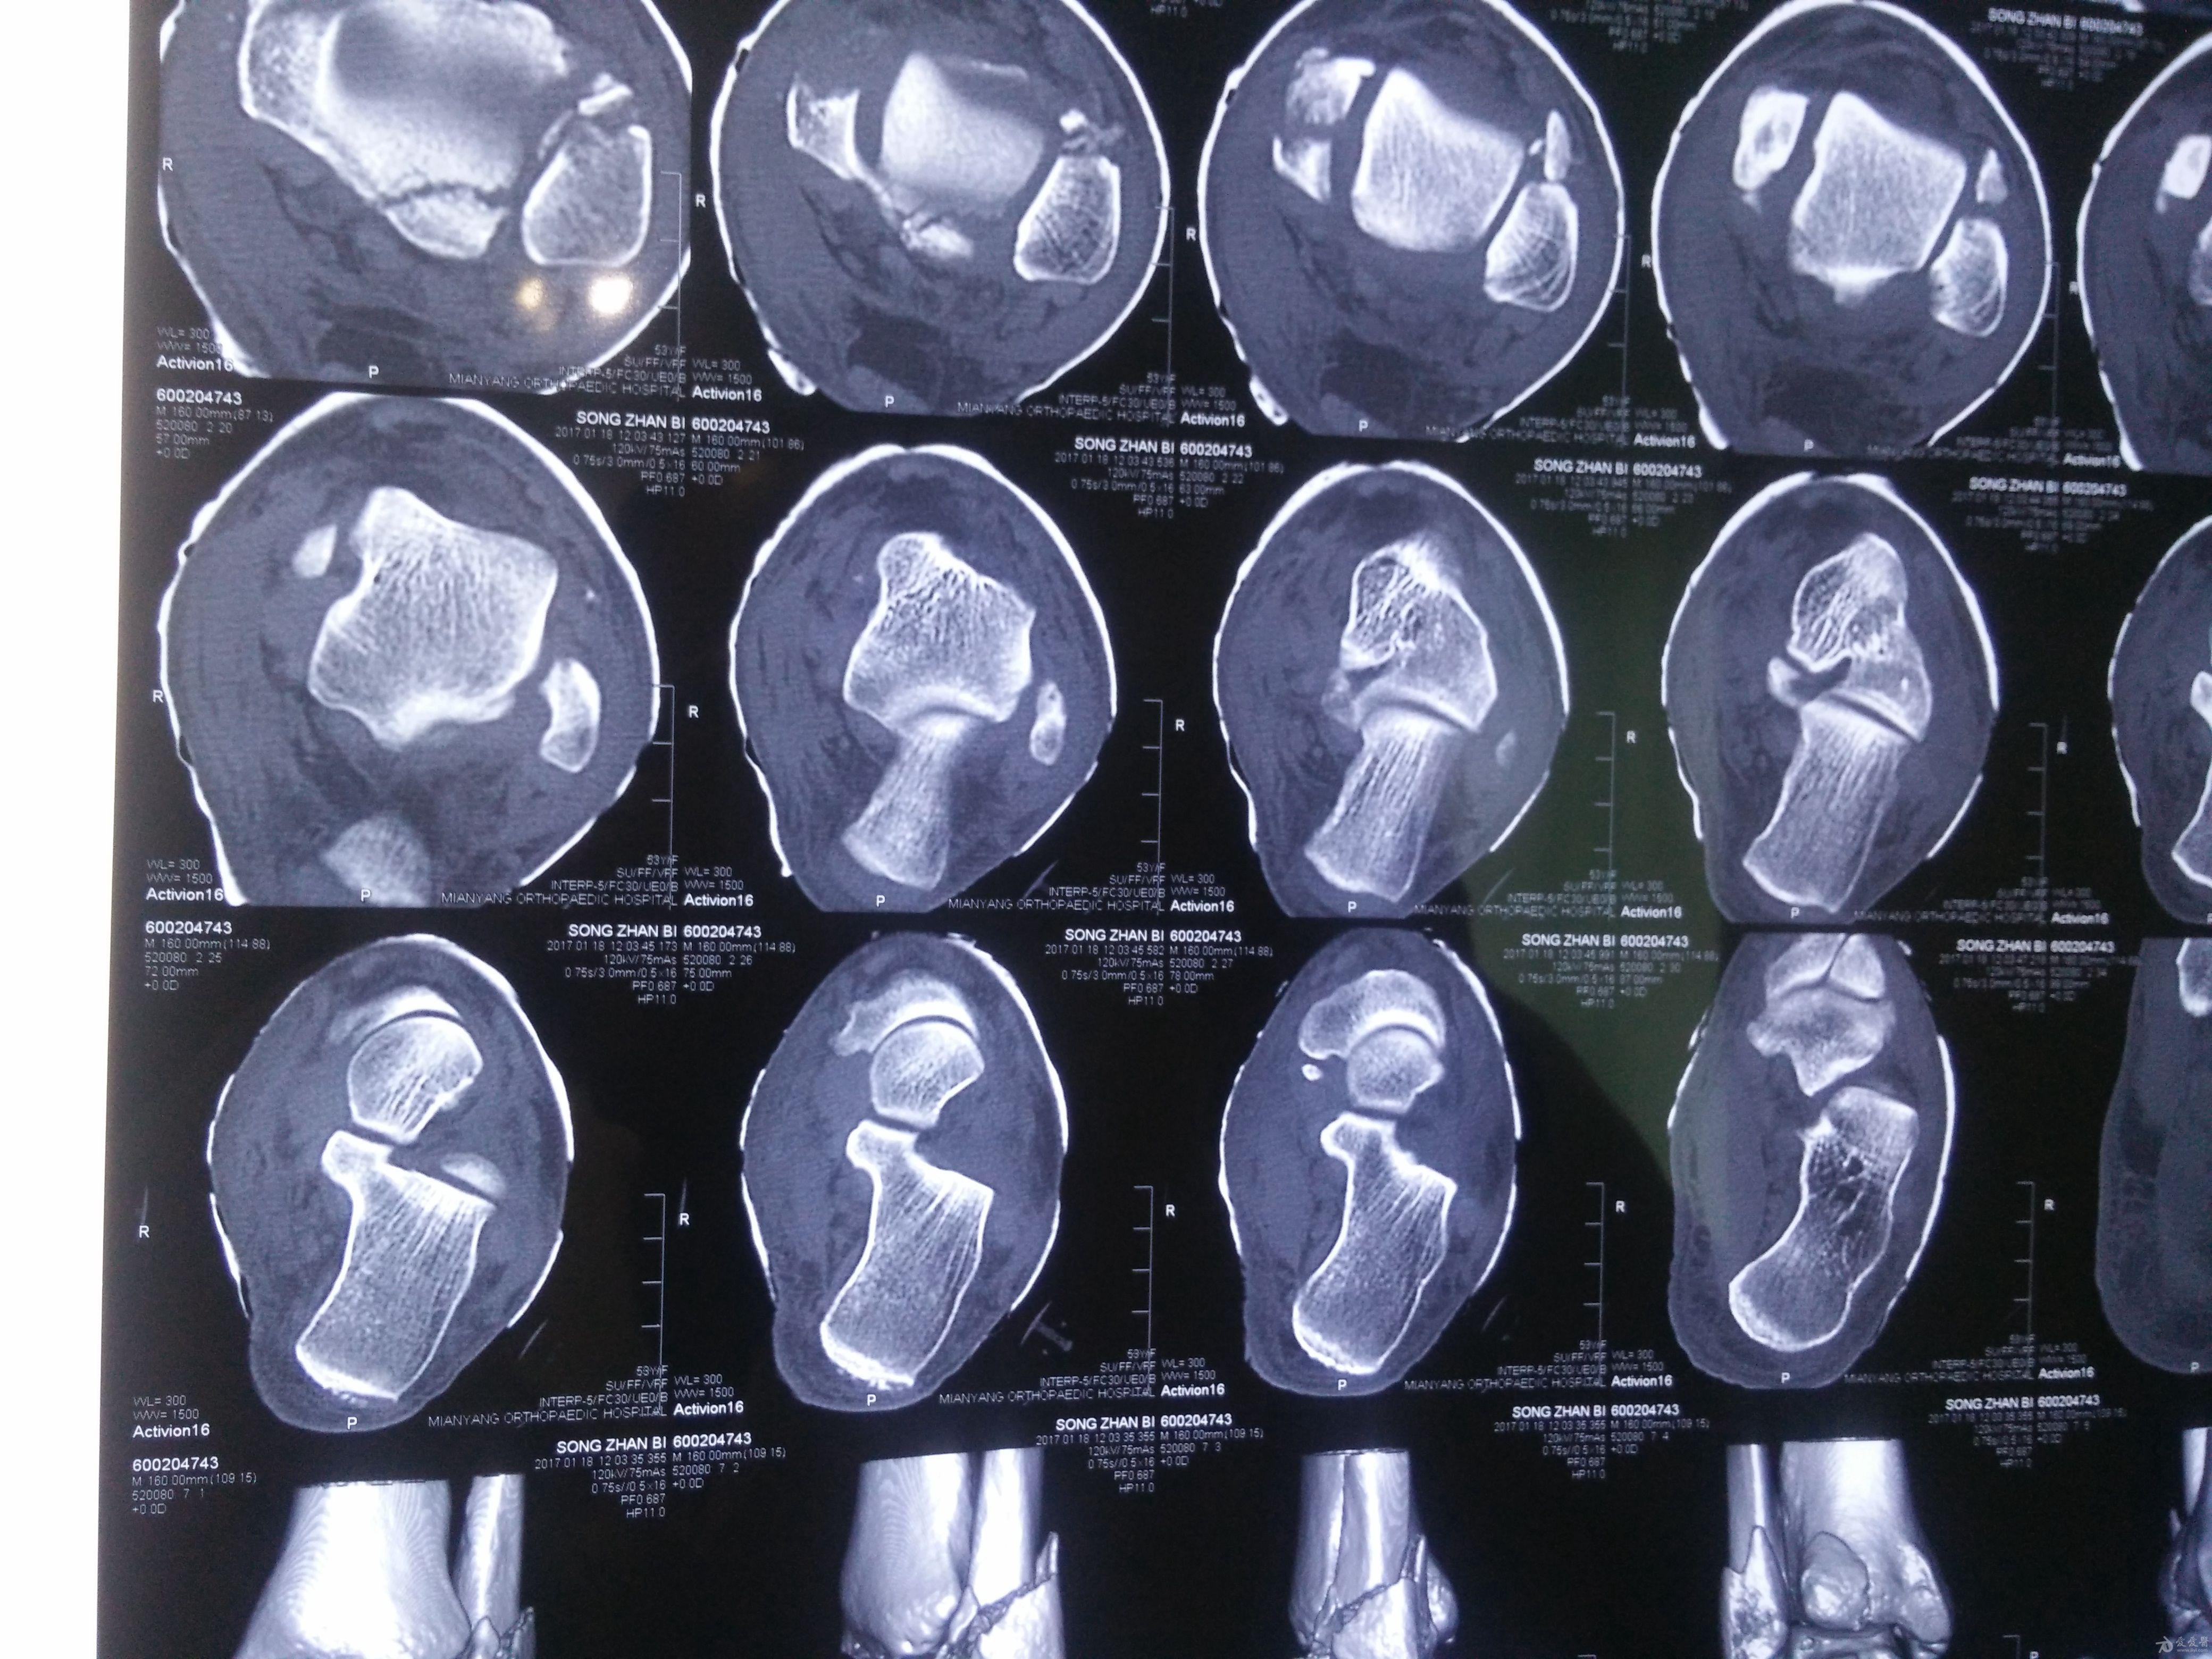

左三踝骨折手术治疗

患者女,外伤后左踝关节活动受限1小时入院,

入院后查体:左踝关节肿胀,活动受限,行DR及左踝关节CT检查,如下图,手术待肿胀消退后行手术治疗,目前愈合良好,请问问各位老师,好久可以下地呀, 下胫腓联合镙钉3个月取呀,